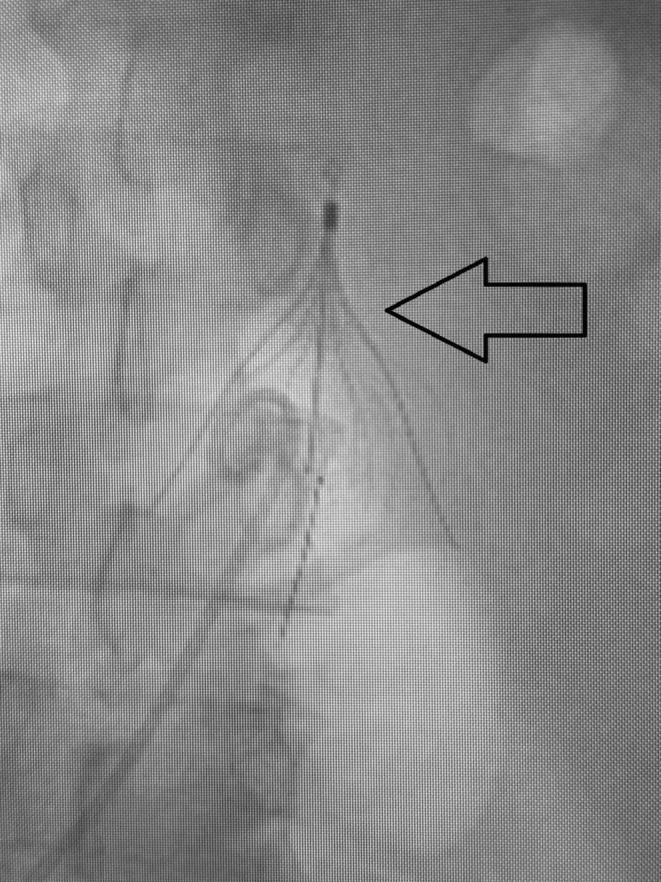

A Novel Approach to an Under-Recognized Entity: Percutaneous Thrombectomy of IVC Filter Thrombosis Complicated With Pulmonary Emboli Using the INARI FlowTriever Device: A Case Report.

Inferior vena cava (IVC) thrombosis, a rare complication of IVC filter insertion, is usually managed with anticoagulation, often insufficient for extensive thrombus. Surgical thrombectomy, effective but invasive, is less favored. Endovascular options like the Inari FlowTriever system are rising in popularity for their mechanical thrombectomy capability without requiring fibrinolytics or ICU admission.